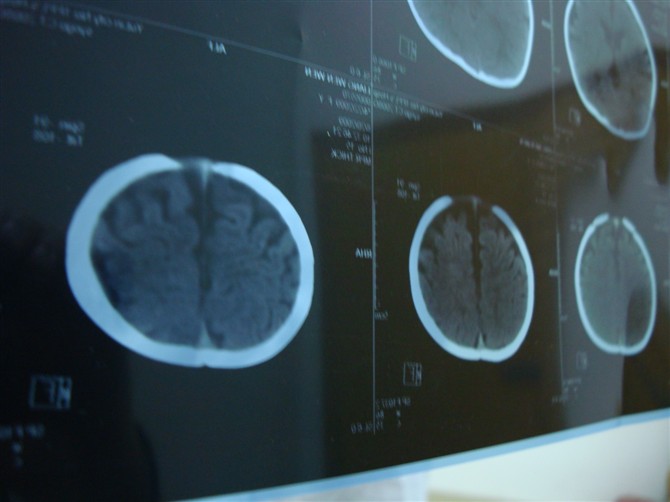

相机照的不太清楚,但还是请各位老师帮忙看下,谢谢!

图像不连续,外部性脑积水诊断问题不大,另外,三脑室上抬,侧脑室间距增宽,支持考虑胼胝体发育不良。